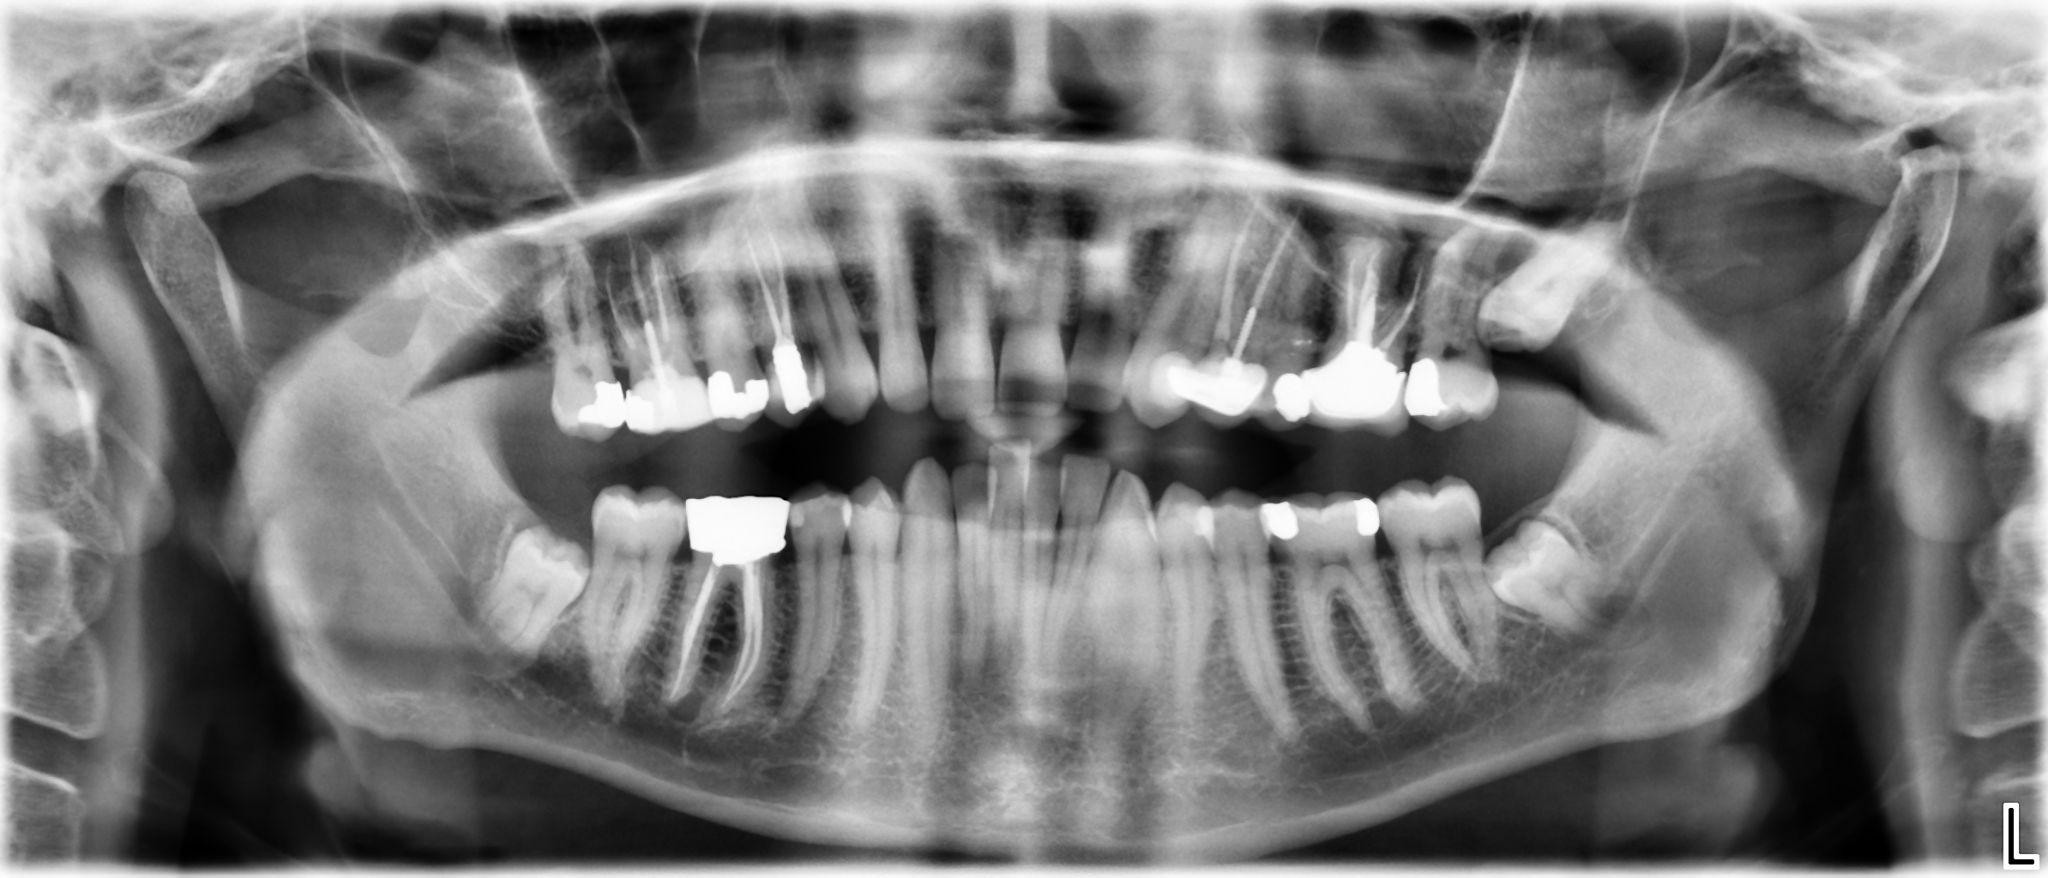

5. What options can be selected for the first quadrant of this panoramic X ray?

6. What options can be selected for the second quadrant of this panoramic X ray?

7. What options can be selected for the third quadrant of this panoramic X ray?

8. What options can be selected for the forth quadrant of this panoramic X ray?